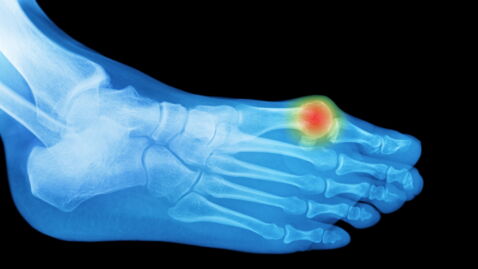

Bunions are not the most talked-about condition. They are commonly found in old people. A bunion is a bump on the side of the big toe. The bump develops gradually over time, and eventually, it becomes so big that it visibly sticks out next to your big toe. Sometimes it even gets big enough that it causes your toe to bend in so far that it overlaps the next toe. This results in difficulty in walking and other mobility issues.

The bunions, scientifically termed hallux abducto valgus, are formed due to years of pressure on the single big toe. Which in turn puts constant pressure on the metatarsophalangeal or MTP joint. The toe joint becomes tilted over time, resulting in the formation of a bony bump.